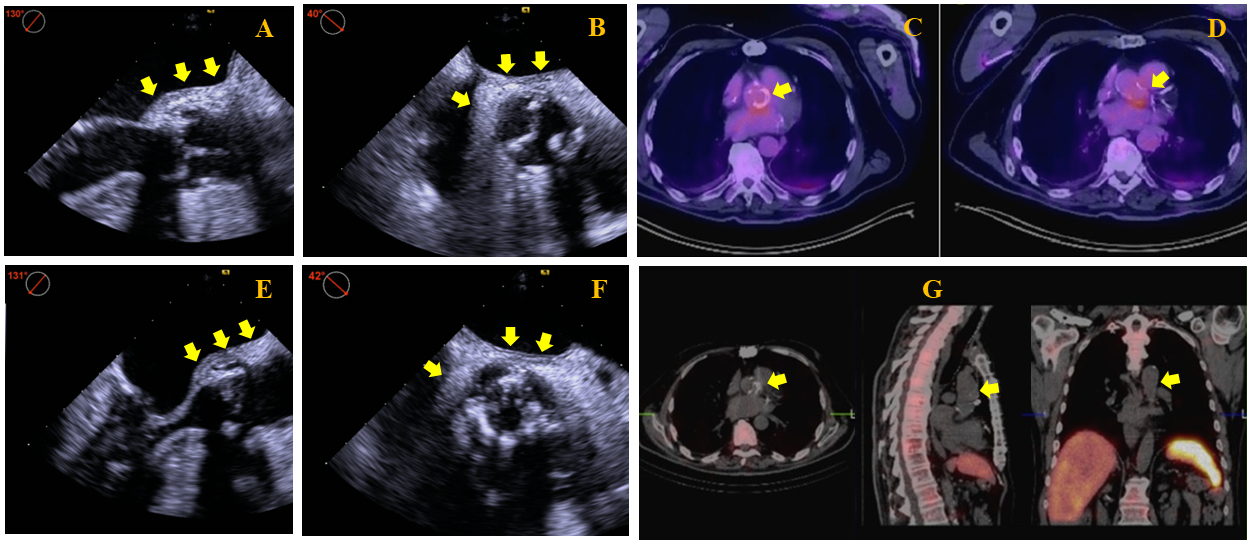

Imaging Findings: Initial technically limited transthoracic echocardiogram was followed by a transesophageal echocardiogram (TEE) that demonstrated a well seated BAV with mildly thickened leaflets but no vegetations, mild intra-valvular regurgitation, and 9 mm end-diastolic soft tissue echoreflectant thickening of the posterior aortic root (AoR) extending up 3 cm from the aortic annulus to the ascending aorta (Fig 1A,B). There were no signs of perivalvular abscess formation. Initial FDG PET-CT demonstrated heterogenous hypermetabolic activity at the annulus of the BAV (Fig 1C) and AoR (Fig 1D) consistent with aortitis.

Decision-making: In the absence of guidelines for the management of these patients, a multidisciplinary team including cardiology, cardiothoracic surgery, and infectious disease opted for a conservative medical therapy instead of high-risk surgery. Patient then underwent left foot first digit amputation to achieve infectious source control. Upon completion of 4 out of 6 weeks of intravenous ceftriaxone 2 grams daily, repeat TEE showed improved AoR thickening to 6 mm (Fig 1E,F), no AoR abscess, and unchanged BAV structure and function. Repeat FDG PET-CT at the same time of TEE demonstrated persistent but improved hypermetabolic activity of the BAV annulus and AoR. After 10 weeks of IV antibiotics, repeat FDG PET-CT showed further decrease in metabolic activity on both areas. However, an Indium-111 labeled leukocyte scan showed no activity at the BAV annulus and root (Fig 1G) and therefore indicated healed AoR aortitis, which was further supported by significant decrease of ESR and CRP initial values of 126 mm/hr and 122.7 mg/L to 11 mm/hr and 3 mg/L, respectively. Patient is currently clinically stable 8 months later.